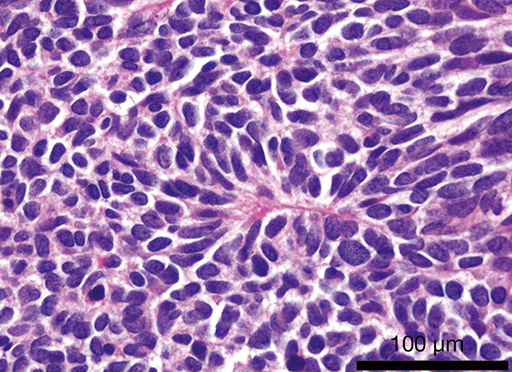

Características de MALIGNIDADE de um nódulo pulmonar?

Qual tipo de CA broncogênio?

ADENOCARCINOMA